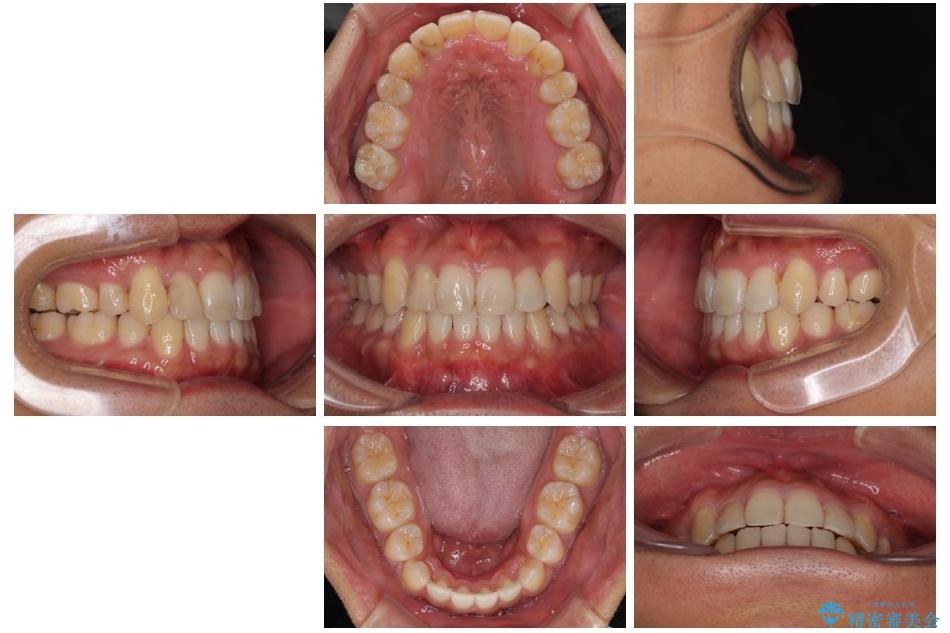

「八重歯を治したい」とご相談いただいた患者様の症例をご紹介します。

上下の前歯部に強い叢生(ガタガタの歯並び)があり、そのまま歯を並べると出っ歯になってしまう可能性がありました。

そこで、上下左右の第一小臼歯を抜歯し、歯が並ぶためのスペースを確保し叢生を解消する治療計画を立てました。

治療前

• 八重歯と前歯のガタガタを抜歯矯正で治療|クリアブラケット使用例 治療前画像